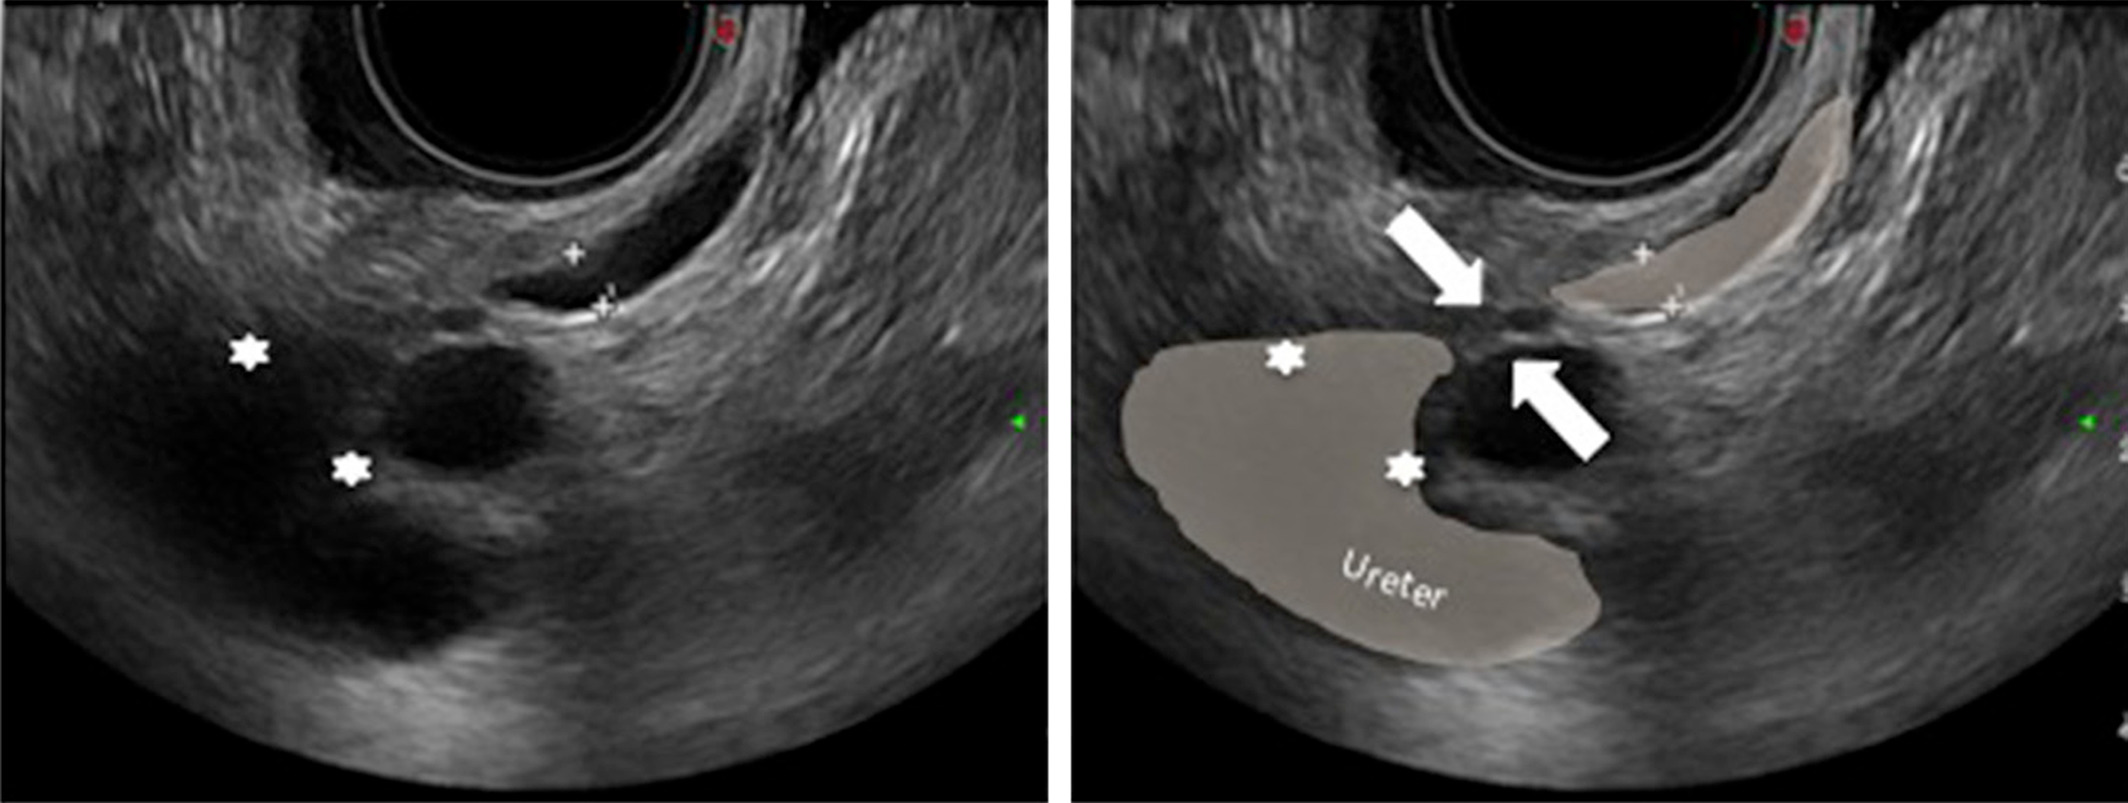

سپس یک پزشک یک لوله نازک و انعطاف پذیر (کاتتر) را در دهانه رحم شما قرار می دهد. یک مایع نمکی به نام سالین از طریق کاتتر به داخل رحم شما فرستاده می شود. در همان زمان، مبدل امواج صوتی را از طریق ژل و به بدن شما ارسال می کند. پژواک این امواج صوتی تصویری در زمان واقعی از داخل رحم شما ایجاد می کند که ساختار رحم شما را نشان می دهد. مایع نمکی به سونوگرافی کمک می کند تا تصویری با جزئیات واضح تر تشکیل دهد.

پزشک ممکن است گرز را کمی حرکت دهد تا تصاویر متفاوتی از رحم شما بگیرد. این تصاویر بر روی صفحه نمایش ویدئویی ظاهر می شوند. این یک سونوگرافی استاندارد واژینال است.

سپس پزشک عصا را دوباره داخل واژن شما قرار می دهد. سالین از طریق کاتتر، از طریق دهانه رحم و به داخل رحم فرستاده می شود. این ممکن است باعث کمی گرفتگی شود. هنگامی که مایع نمکی کافی رحم شما را پر می کند، تصاویری از داخل رحم شما گرفته می شود.